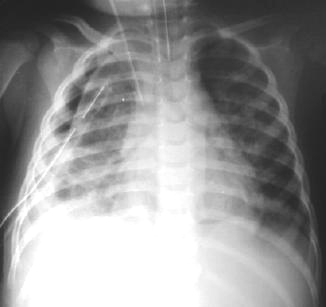

Radiología del tórax Post-operatoria

Rx.Tórax Pa. 24 horas post operatorio UTIPediatrica: Expansión pulmonar completa, el drenaje del tórax, disminución del volumen pulmonar derecho, mediastino levemente lateralizado a la derecha, tubo endotraqueal para ventilacion mecánica asistida